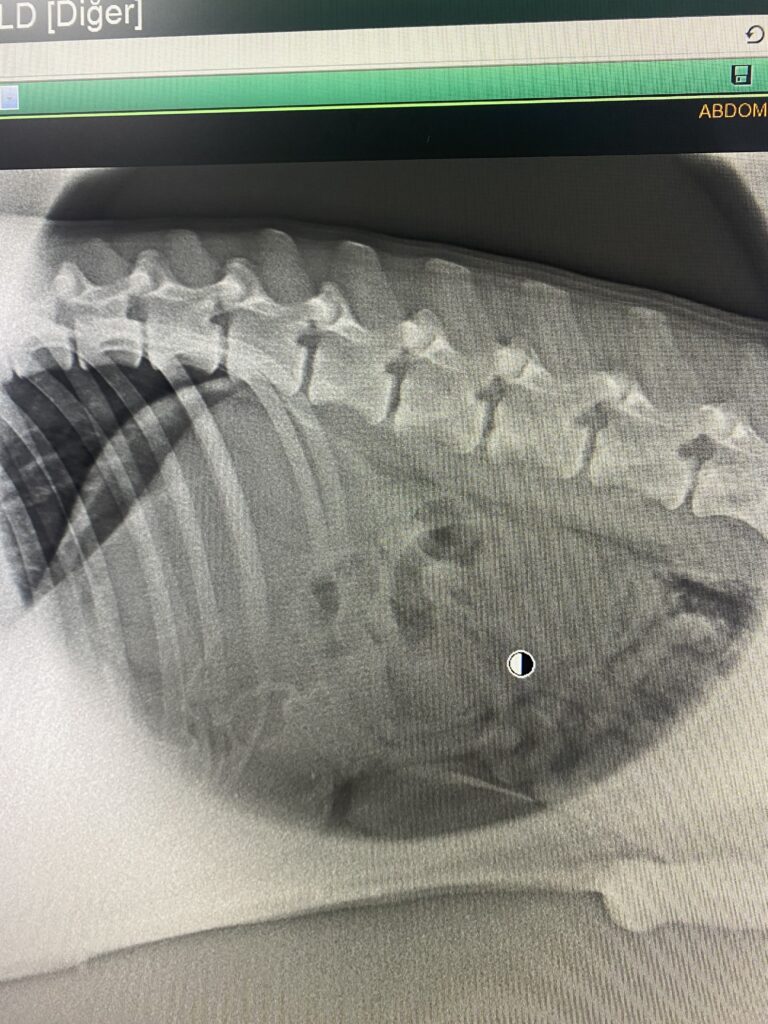

Eğer köpeğinizin yabancı bir cisim yuttuğunu fark ettiyseniz, veteriner hekime danışmadan asla kusturmaya çalışmayın. Keskin bir cisim (kemik parçası, plastik) kusma sırasında yemek borusuna çok daha büyük zarar verebilir. İlk yapmanız gereken şey, zaman kaybetmeden en yakın hayvan hastanesine giderek röntgen veya ultrason çekilmesini sağlamaktır. Bazı küçük ve yumuşak nesneler diyet değişikliği ile doğal yollarla çıkabilirken, ipli veya sert nesneler genellikle cerrahi müdahale gerektirir.